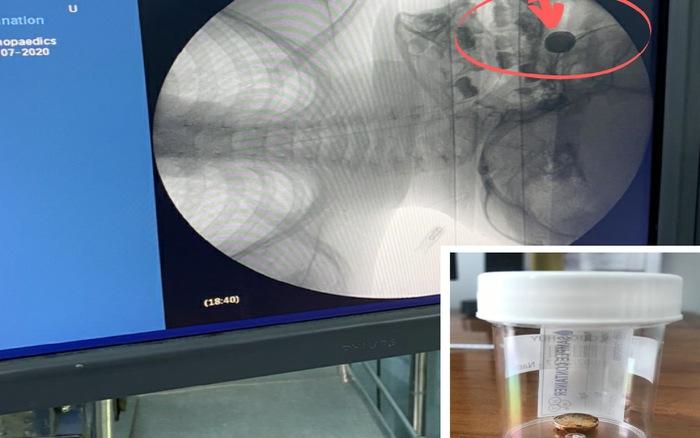

Tại bệnh viện, các bác sĩ chỉ định chụp X-quang cho bệnh nhi, phát hiện dị vật hốc mũi và tiến hành lấy dị vật bằng phương pháp gây tê. Tuy nhiên, do dị vật nằm rất sâu trong hốc mũi, mũi chảy máu nhiều và axit của pin đang gây phá hủy hốc mũi và thành mũi.

Tiến hành hội chẩn, các bác sĩ quyết định chuyển sang lấy dị vật bằng phương pháp gây mê. Sau 2 giờ phẫu thuật bằng phương pháp nội soi, dị vật đã được lấy ra thành công.